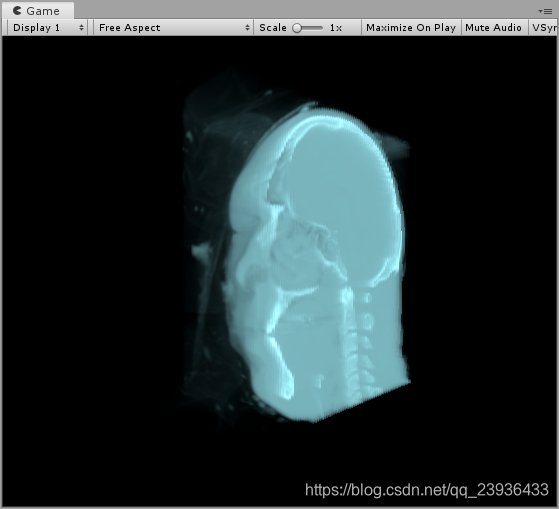

最后我们可能还想获得剖面,那么我们可以通过控制射线取样来实现。简单来说,就是本来射线是从StartPoint出发,一路贯穿几何体进行取样,这里我们进行一些处理,使得射线从我们的剖面位置才开始取样,这样就可以画出剖面,效果如下:

当然我们也可以获得一个水晶剖面的头骨: